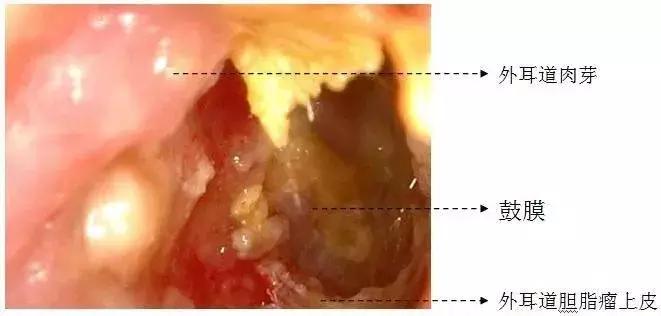

苏立众主任经过详细询问病史后,采用视频耳内镜检查,发现小林的左耳外耳道口肉芽增生,几乎完全堵塞外耳道,清除部分肉芽后进一步检查外耳道有白色豆渣样组织。根据丰富的临床经验,苏立众认为这很可能是外耳道胆脂瘤。没想到,一听是瘤,小林吓得”哎呀”一声轻喊,随即眼泪突眶而出。

该病早期一般无明显不适,后期可出现耳堵塞感、听力下降,若继发了感染,还会出现耳痛、流脓(血)性分泌物,伴特殊臭味等症状。检查时可以见到外耳道内有灰白色或黄色角蛋白碎屑、上皮样物堵塞,表面被多层鳞片状物包裹,外耳道皮肤充血、肿胀、糜烂,可伴有肉芽形成。必要时还可做颞骨CT检查,以确定是否有骨质破坏。